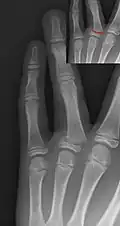

Salter–Harris II fracture of ring finger proximal phalanx.